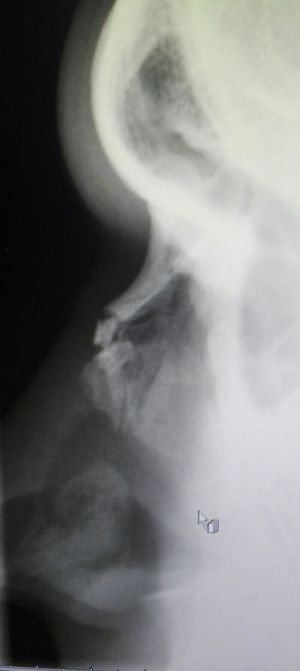

Xray

Fracture

Nose